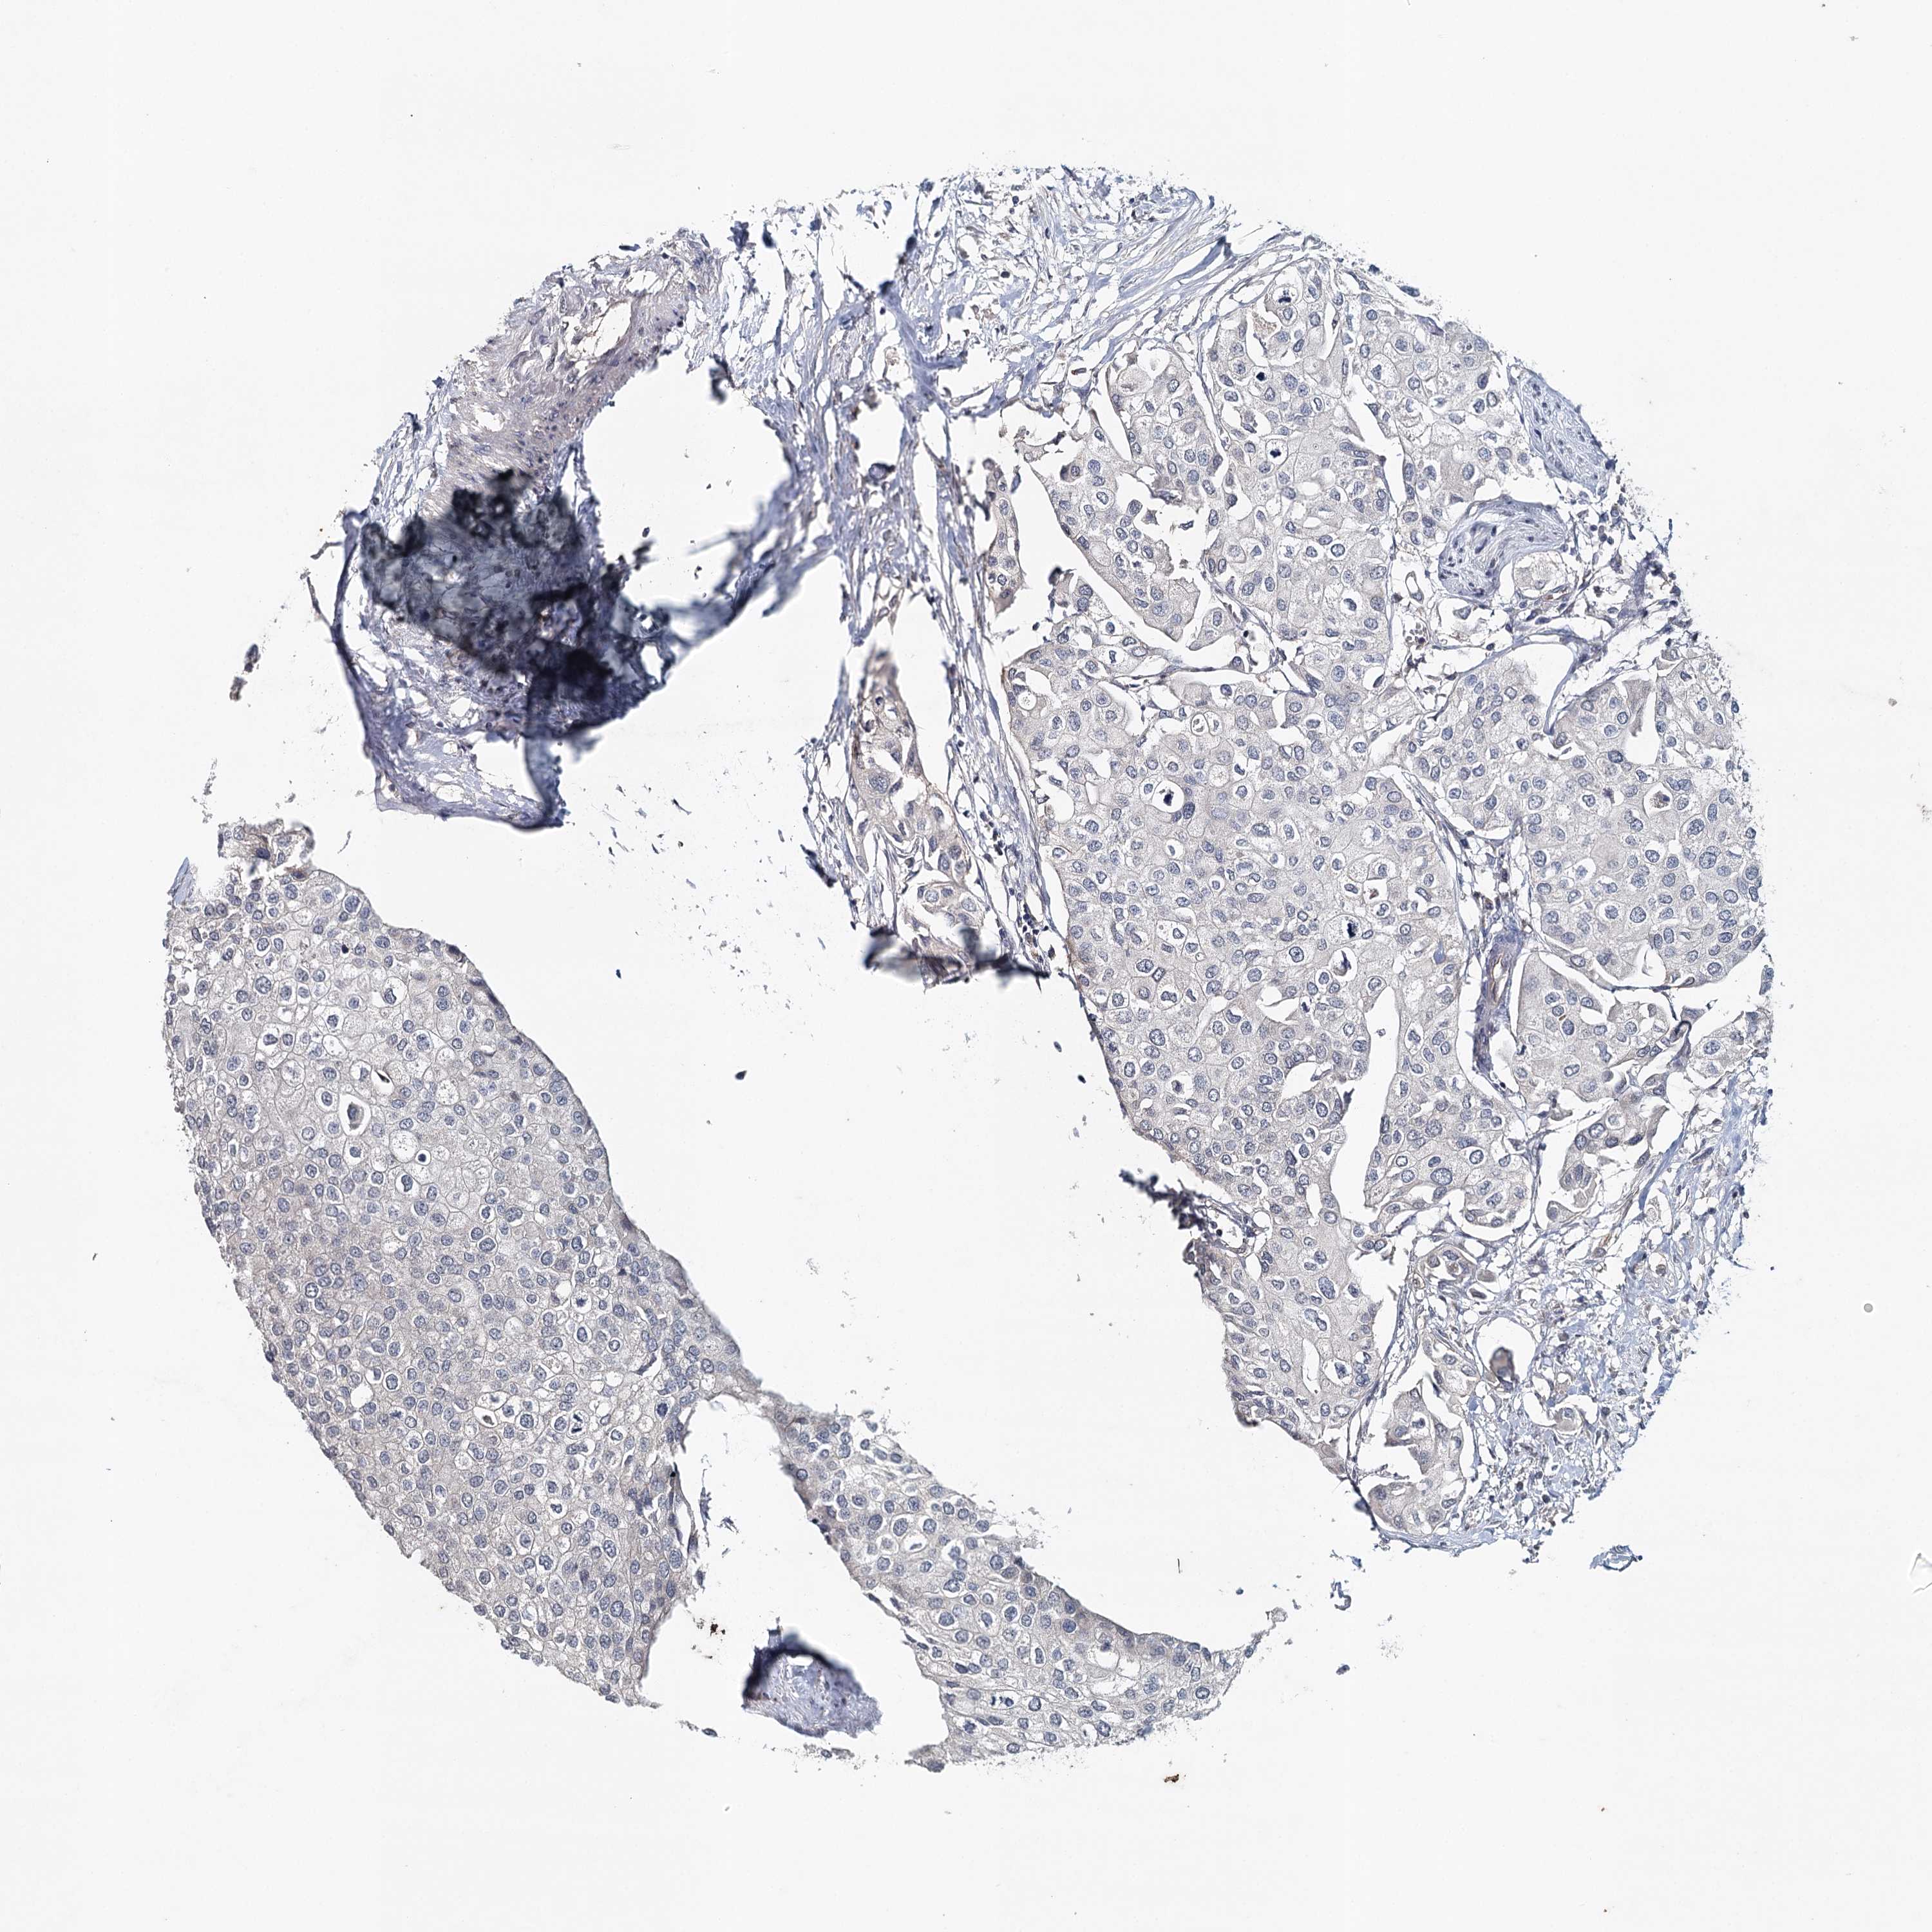

UROTHELIAL CANCER - Protein expressioni

A mouse-over function shows sample information and annotation data. Click on an image to view it in a full screen mode. Samples can be filtered based on level of antibody staining by selecting one or several of the following categories: high, medium, low and not detected. The assay and annotation is described here.

Antibody stainingi

Antibody staining in the annotated cell types in the current human tissue is reported as not detected, low, medium, or high, based on conventional immunohistochemistry profiling in selected tissues. This score is based on the combination of the staining intensity and fraction of stained cells.

Each image is clickable and will lead to virtual microscopy that enables deeper exploration of all samples and also displays staining intensity scores, fraction scores and subcellular localization as well as patient and tissue information for each sample.

Antibody HPA034631

Antibody HPA071347

Antibody CAB033265

Antibody CAB037325

Urothelial carcinoma, High grade

Urothelial carcinoma, Low grade

Urothelial carcinoma, NOS